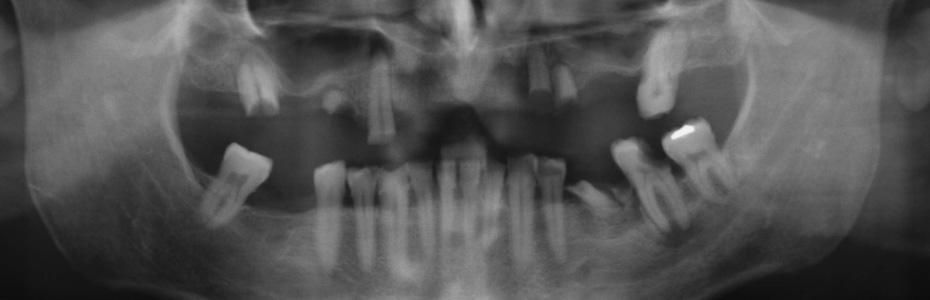

Implantologische Misserfolge

Ein Misserfolg muss nicht immer ein Implantatverlust sein. Auch eine Abweichung von dem mit dem Patienten geplanten und dem erzielbaren Ergebnis kann als Misserfolg verstanden werden.

Vom Misserfolg zur erfolgreichen Behandlung

Unkenntnis oder Versäumnisse

Implantologische Misserfolge können auf Unkenntnis von Begleitumständen und einer ungünstigen Abfolge von Ereignissen oder Versäumnissen beruhen.

Wir zeigen Ihnen an dieser Stelle Patientenfälle, die vorbehandelt in die Praxisklinik für dentale Implantologie gekommen sind und für die wir im Rahmen einer Weiterbehandlung eine Lösung gefunden haben. In vielen Fällen haben wir festgestellt, dass die Misserfolge vorhersehbar und vermeidbar gewesen wären.